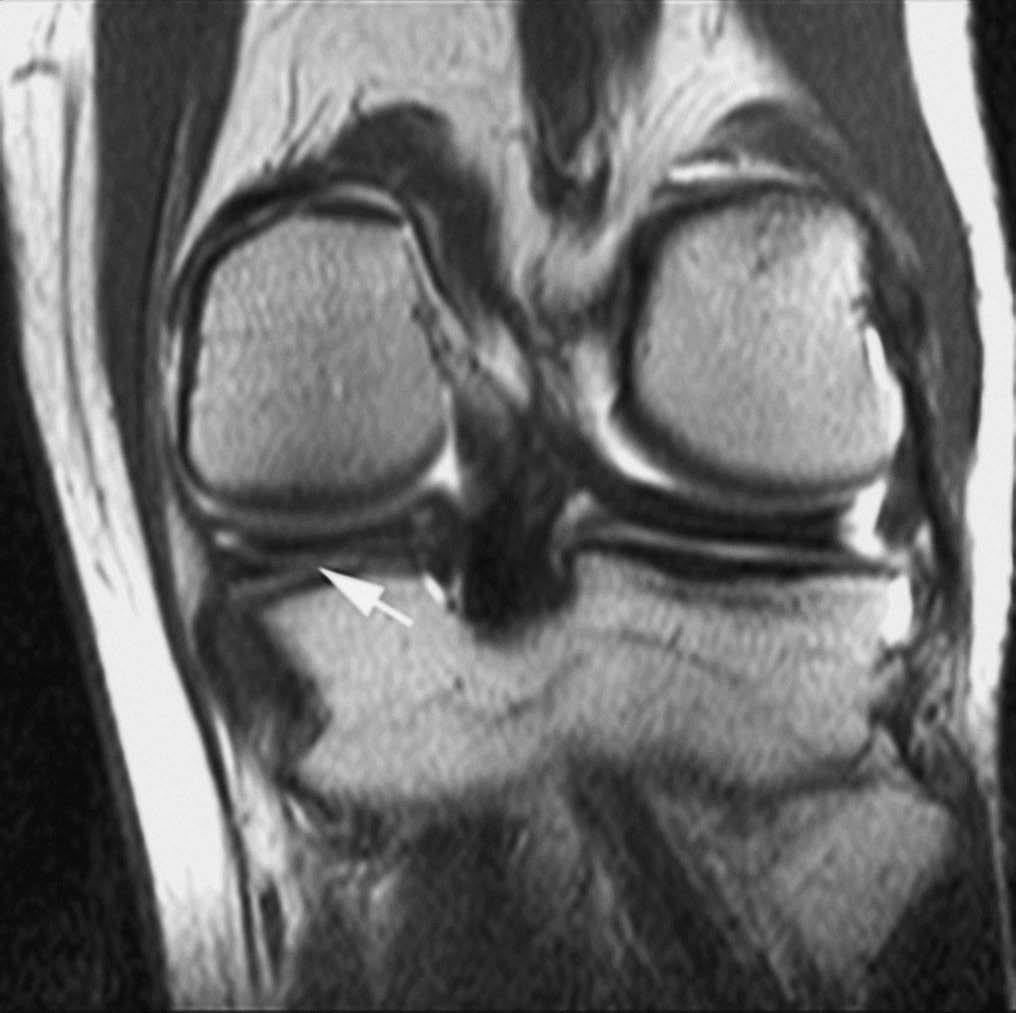

La RMA es una técnica con mayor eficacia diagnóstica en la valoración de las roturas meniscales recurrentes. Después de meniscectomías parciales, la capacidad de diagnosticar roturas recurrentes depende de la cantidad de menisco extirpado. Cuando la resección meniscal es menor del 25% los criterios de rotura en RM son los mismos que en la rodilla no operada --la fiabilidad de la RMA es similar a la de la RM en estos casos--. Cuando la resección es mayor del 75% la clínica del paciente no se asocia a las rerroturas meniscales. En los casos de resección entre el 25 y el 75% los criterios de rerrotura se basan en la introducción de contraste en el remanente meniscal (fig. 6)1,15,16.

Fig. 6.--Rerrotura de asta posterior del menisco interno. A, B) Corte coronal potenciado en T1 y corte sagital de RMA potenciado en T1 con técnica de supresión grasa en los que se observa introducción del contraste en el defecto meniscal.